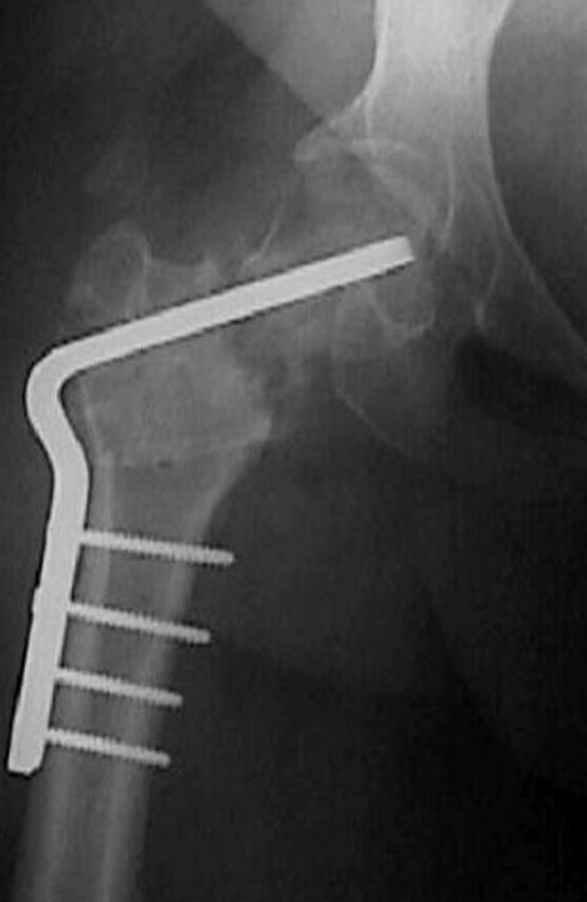

На рисунке N1 предоперационный план лечения ложного сустава шейки бедра- линия ложного сустава, угол и направление введения импланта, клиновидная остеотомия в градусах и миллиметрах, второй снимок после коррекции, расчет, на сколько удлиняется конечность и размеры импланта;

N3 рисунок окончательный снимок, после операции моя рентгенограмма должен выглядеть примерно как эта картина. На N4 снимке клин перед удалением; N5 послеоперации 3 нед.; N6 окончательная рентгенограмма.

варус при проксимальном отделе 95 градусной пластиной.